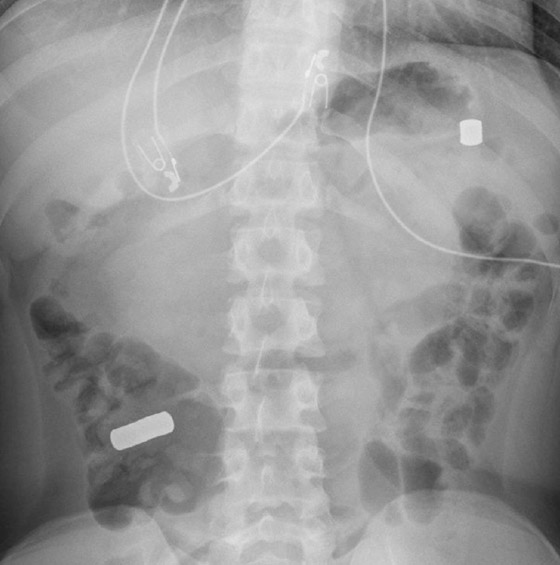

تم الإبلاغ أخيرًا في الولايات المتحدة عن مراهق ابتلع أكثر من اثني عشر مغناطيسًا، وكل ذلك دون أن يتذكر. وشعر المراهق بتقلصات بطن مؤلمة، ذهب على أثرها إلى قسم الطوارئ في المستشفى حيث كشفت عمليات المسح عن وجود أجسام معدنية في معدته وأمعائه، وأكدت المزيد من الأشعة المقطعية والأشعة السينية وجود نوع ما من العناصر المعدنية.

لقد بدوا بشكل مثير للريبة مثل مغناطيس النيوديميوم الفائق القوة، حيث أن المغناطيسات كانت موجودة في قرحة في جدار المعدة لفترة كافية لبدء التسبب في بعض الضرر. وتمت إزالة المغناطيسات بسهولة نسبية باستخدام ملقط وشبكة جراحية صغيرة، إلا أن المزيد من التحقيقات خلال اليومين التاليين أظهرت أن عملهم لم ينته بعد. وسرعان ما تم اكتشاف المزيد من المغناطيسات تتحرك عبر الأمعاء الغليظة، حيث ظهرت بالفعل علامات التعفن.

وعلى الرغم من إمكانية إزالة ثلاثة منها أثناء تنظير القولون، إلا أن الباقي يتطلب عملية جراحية، حيث تم الكشف عن 15 مغناطيسًا إضافيًا. ويبدو أن المغناطيسات ضغطوا جزءا من الأمعاء الغليظة والدقيقة بالفعل وبدأوا بصنع ثقب في الأمعاء. ليست هناك حاجة لشرح العواقب المروعة للأمعاء المثقوبة. ولحسن الحظ، فإن إزالة المغناطيس وبعض المضادات الحيوية في الوقت المناسب منعت المراهق من الشعور بألم ثقب في أمعائه وتسريب محتوياته إلى بطنه.